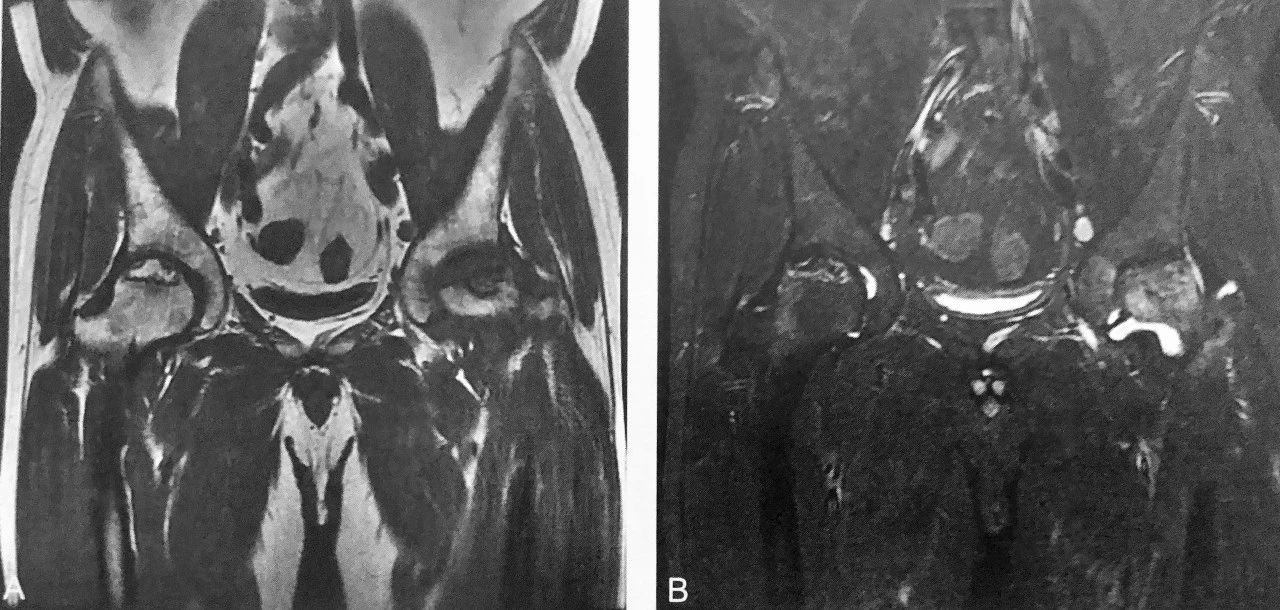

双 线 征

A. T1WI 冠状位见右侧股骨头线状低信号;B T2WI 冠状位压脂见与线样低信号平行排列的线样高信号,高低相间信号同时存在的双线征

判读要点:

1、双线征是 ARCO 分期 Ⅱ 期股骨头缺血性坏死的直接征象;

2、双线征对诊断期股骨头缺血性坏死具有特异性;

3、双线征在 MRI 图像上显示;

4、MRI 对股骨头缺血性坏死的早期诊断优于 CT 和 Ⅹ 线。